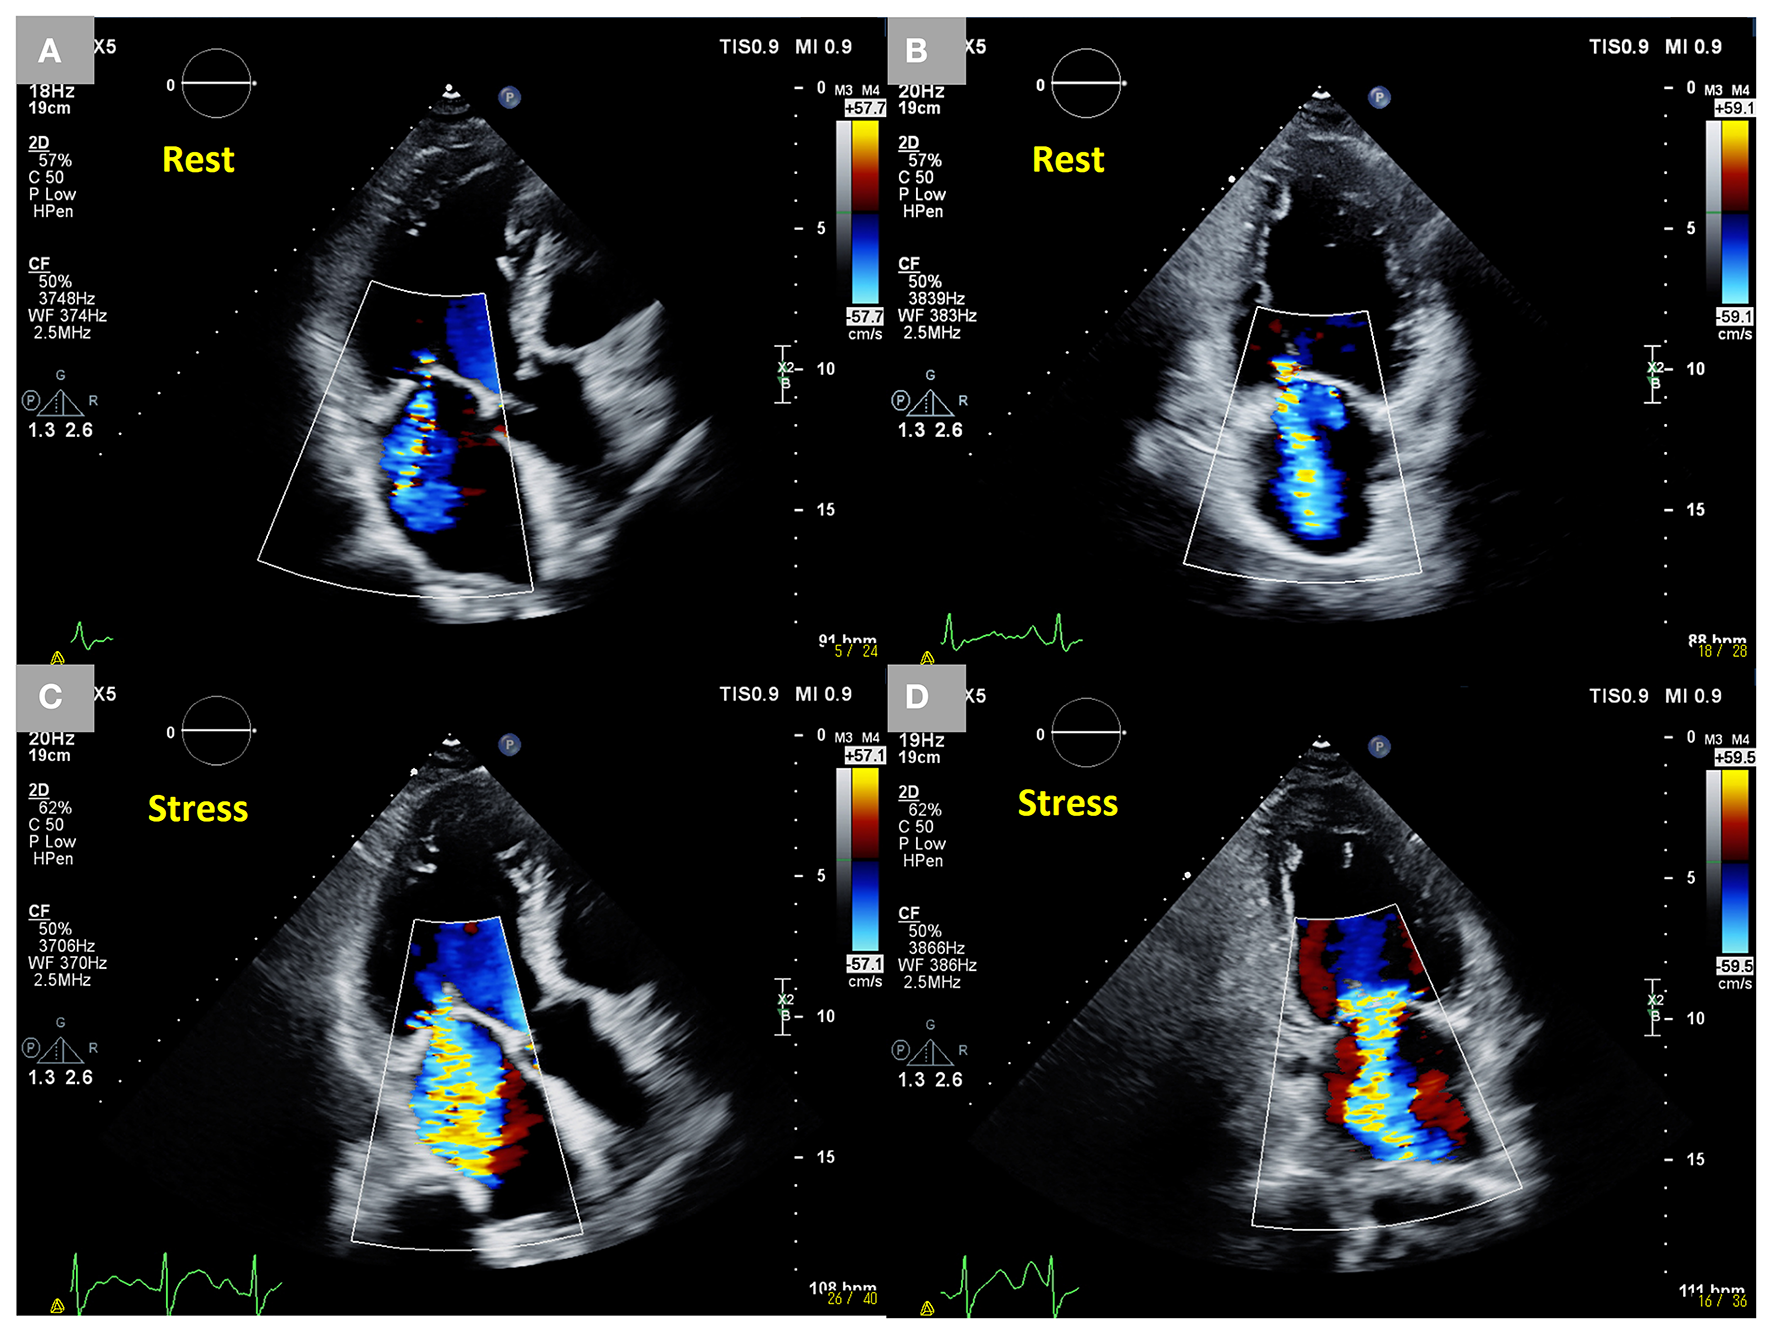

Figure 2

Dynamic changes in SMR during exercise stress echocardiography in an 85-year-old male patient who had an anterior old myocardial infarction and heart failure with reduced ejection fraction. Moderate SMR (EROA 0.22 cm2) at rest. (A,B) Two-dimensional color Doppler images from three- and two-chamber views. Dynamic severe SMR (EROA 0.46 cm2) under stress. (C,D) Two-dimensional color Doppler images from three-chamber and two-chamber views. SMR, secondary mitral regurgitation; EROA, effective regurgitant orifice area.